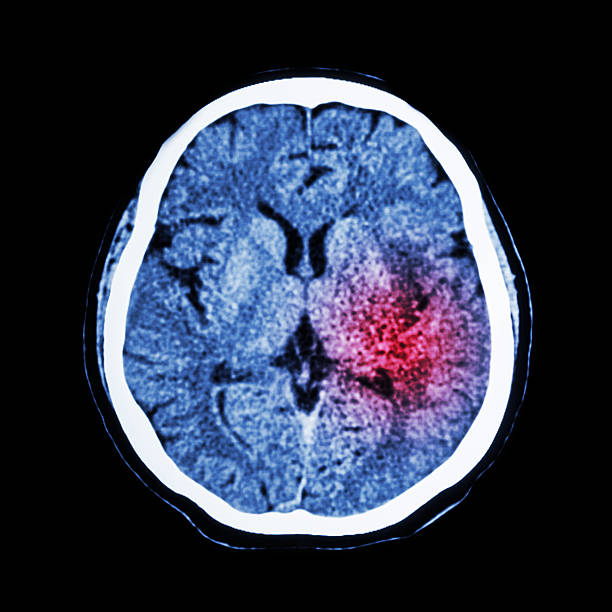

뇌출혈 전조 증상 자세히 알아보기

뇌출혈은 뇌안에 있는 혈관에서 출혈이 발생하여 뇌조직이 손상을 입는 질환이며, 중증의 뇌혈관질환 중 하나입니다. 일반적으로 고혈압, 동맥류, 혈관 기형, 혈전 등의 이유로 혈관이 파열하거나 뚫리면서 발생합니다.

뇌출혈은 갑작스러운 발작, 의식 잃음, 경련, 혼란, 언어 장애, 편마비 등의 증상을 일으키며, 이러한 증상이 발생하면 즉시 의료진의 진료를 받아야 합니다. 뇌출혈은 치료가 지연되면 심각한 후유증을 일으킬 수 있으므로, 조기 발견과 적절한 치료가 필요하기 때문에 이번 시간에는 뇌출혈 전조 증상에 대해 자세히 알아보겠습니다.